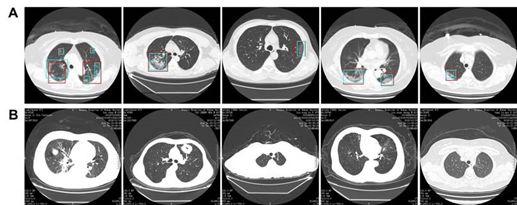

在11例covid19肺炎患者的4382张CT图像和31例对照组患者的9369张CT图像中,模型对患者的诊断正确率分别为100%,特异性为93.55%,正确率为95.24%,PPV为84.62%,NPV为100%。每幅图像的灵敏度为94.34%,特异性为99.16%,准确度为98.85%,PPV为88.37%,NPV为99.61%。模型预测的代表性图像如图4所示。

图4 模型预测的代表性图像。A. COVID19肺炎的CT图像。人工智能模型和放射学家的预测是一致的。绿色方框,放射科医生的标签; 红色的盒子,模型的标签。B.对照组CT图像。第一张是普通细菌性肺炎,显示右下肺叶实变。第二张图片为肺部肿瘤病变,左上肺叶有肿块,边缘有毛刺,叶状生长,内部有液泡。第三张图片是继发性肺结核,显示左侧根尖纤维束。第四张图片为支气管扩张合并感染,表现为支气管扩张、扩张、囊性改变及周围感染斑块。第五张图显示的是正常的肺。